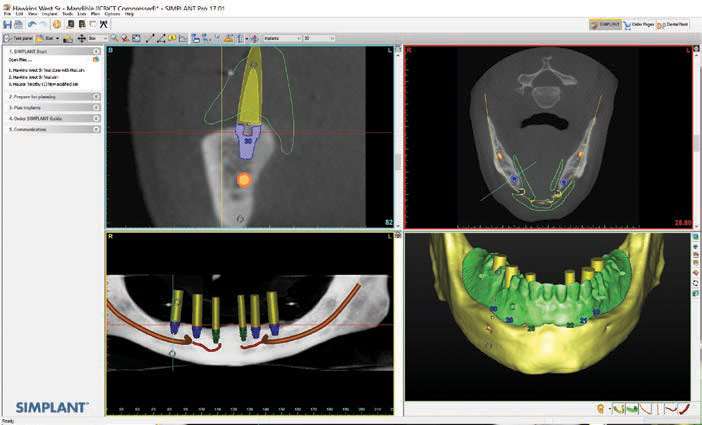

After the patient had the upper partial denture and lower denture fabricated and the vertical dimension of occlusion, aesthetics, and phonetics were verified, the approved lower denture was used as a vehicle for fiduciary markers so that a CBCT scan could be done. If needed, a surgical guide could be fabricated from a dual-scan protocol (Suremark) (Figure 4).

In this case, the DICOM images were submitted to 3DDX so that the CBCT scan could be reformatted and used to fabricate a mucosa or bone-supported surgical guide. 3DDX is a company that offers implant treatment planning, radiology reports, surgical guide fabrication, and support to ensure the clinician can provide a smooth and seamless surgery. After assessing the reformatted CBCT scan, coDiagnostiX software (Dental Wings) was used to virtually place implants within the confines of the scanned denture. This was done to ensure that the implants would be prosthetically guided and placed within the confines of the verified denture construct (Figure 5). Typically, reformatted images and fine-tuning sessions can be done within a week to expedite surgeries. As the planning was done, the extent of the mandibular atrophy could be appreciated as well as visualizing additional anterior segments to the inferior alveolar nerve and artery. A radiology report was sought, and it confirmed these anatomic aberrations so that they could be appropriately considered in the implant-planning stages.[5]